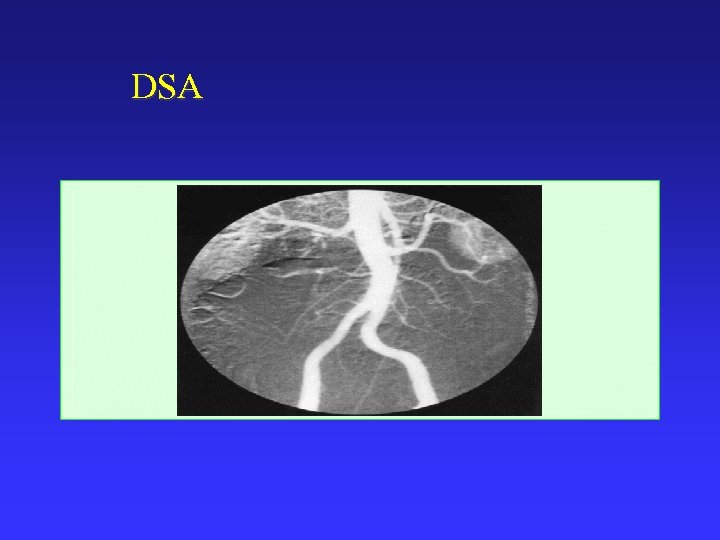

DSA

Terms CT: computerized tomography MRI: magnetic resonance imaging PET: positron emission tomography SPECT: single photon emission tomography DSA: digital subtraction angiography PACS: picture archiving and communication system